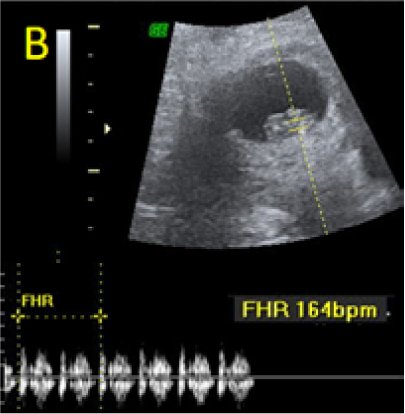

A 22-year-old secundigravida, presented to our Hospital with acute pelvic pain and vaginal bleeding. Her medical history included a 2-year prior caesarean delivery. The patient was in a stable condition and the clinical exam was unremarkable. As the urinary pregnancy test was positive, a transvaginal ultrasound scan was performed to evaluate the pregnancy location and viability. The exam revealed an empty uterine cavity but identified the gestational sac at the level of the caesarean scar with a live embryo (174 beats per minute), measuring 8 weeks and 5 days by crown-rump length. (Figures 1). Because the trophoblastic tissue was noted with an anteriorly location, urinary bladder invasion was suspected based on the ultrasonographic signs: poor identification of the bladder wall, the lack of the sonolucent space and increased vascularization with abnormal pattern (Figure 2). The patient blood tests results were normal, and beta-human chorionic gonadotropin (b-HCG) value was 145.000mUI/ml. After proper counselling and written informed consent the patient opted for a medical conservative treatment with desire to preserve her fertility.

Figure 1. A: the gestational sac is located at the level of the uterine isthmic scar, grey-scale and Power Doppler transvaginal evaluation. B: an embryo with a crown-rump length (CRL) that corresponds to 8 weeks and 1 day is found with normal fetal heart activity (C).